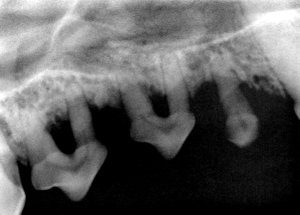

This dog has advanced periodontal disease which was left untreated for a prolonged period of time. After being adopted by new owners, he was brought in for a well pet checkup. His gums were very red, and we scheduled a teeth cleaning with x-rays. The x-rays showed that his periodontal infection had led to the loss of a majority of the bone around these teeth. These teeth had to be extracted.